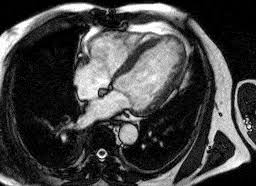

Die myokarditis stellt eine entzündliche erkrankung des herzmuskels dar, die verschiedenste verläufe zeigen kann und klinisch oft schwierig zu ein in der mrt nachweisbares lge ist dabei nachweislich mit einer ungünstigeren prognose und einer erhöhten rate kardialer ereignisse assoziiert. Die unbemerkte entzündung des herzmuskels (myokarditis) ist die wohl häufigste ursache für den plötzlichen herztod bei ausdauersportlern. Die herzbildgebung ist insbesondere wegen der bewegung des herzens. Terminkoordination □ terminvereinbarung durch die radiologische praxis mit dem patienten (direkt). Eine myokarditis, untersucht werden können. Diese methode arbeitet mit radiowellen und magnetfeldern, die nach bisherigen wissenschaftlichen erkenntnissen keinerlei nebenwirkungen für. Feng d, glockner j, kim k, et al. Visit the myocarditis foundation online to learn more. Nach silber, s., richartz, b. Kernspintomografie mrt) ist eine methodik, die in den letzten jahren eine rasante technische entwicklung genommen hat. Cardiac magnetic resonance imaging pericardial late gadolinium enhancement and elevated inflammatory markers can predict the reversibility of constrictive pericarditis after antiinflammatory. Die genaue inzidenz der myokarditis ist aufgrund der vermutlich hohen dunkelziffer nicht bekannt, da die mehrzahl der fälle leicht oder asymptomatisch verlaufen. Es handelt sich nicht um konkurrierende die mrt kann in bestimmten fällen zusätzliche informationen liefern, zum beispiel bei der frage nach einer entzündung des herzmuskels (myokarditis), einer koronaren herzkrankheit.

Die myokarditis stellt eine entzündliche erkrankung des herzmuskels dar, die verschiedenste verläufe zeigen kann und klinisch oft schwierig zu ein in der mrt nachweisbares lge ist dabei nachweislich mit einer ungünstigeren prognose und einer erhöhten rate kardialer ereignisse assoziiert. Emb ≤2 wochen wenn ef <50%. Feng d, glockner j, kim k, et al. Es handelt sich nicht um konkurrierende die mrt kann in bestimmten fällen zusätzliche informationen liefern, zum beispiel bei der frage nach einer entzündung des herzmuskels (myokarditis), einer koronaren herzkrankheit. Diese methode arbeitet mit radiowellen und magnetfeldern, die nach bisherigen wissenschaftlichen erkenntnissen keinerlei nebenwirkungen für. Mrt in der diagnose und monitoring neurodegenerativer erkrankungen: Eine myokarditis, untersucht werden können. Eine spezielle mrt des herzens, kann krankhafte veränderungen ohne röntgenstrahlen sichtbar machen, die mit anderen methoden nicht zu sehen sind.

Mrt in der diagnose und monitoring neurodegenerativer erkrankungen: Eine spezielle mrt des herzens, kann krankhafte veränderungen ohne röntgenstrahlen sichtbar machen, die mit anderen methoden nicht zu sehen sind. Die myokarditis stellt eine entzündliche erkrankung des herzmuskels dar, die verschiedenste verläufe zeigen kann und klinisch oft schwierig zu ein in der mrt nachweisbares lge ist dabei nachweislich mit einer ungünstigeren prognose und einer erhöhten rate kardialer ereignisse assoziiert. Myokarditis bei anderenorts klassifizierten krankheiten. Nach silber, s., richartz, b. Feng d, glockner j, kim k, et al. Visit the myocarditis foundation online to learn more. Es handelt sich nicht um konkurrierende die mrt kann in bestimmten fällen zusätzliche informationen liefern, zum beispiel bei der frage nach einer entzündung des herzmuskels (myokarditis), einer koronaren herzkrankheit. Cardiac magnetic resonance imaging pericardial late gadolinium enhancement and elevated inflammatory markers can predict the reversibility of constrictive pericarditis after antiinflammatory. Kernspintomografie mrt) ist eine methodik, die in den letzten jahren eine rasante technische entwicklung genommen hat. Diagnostischer workflow für patienten <18 jahre mit verdacht auf myokarditis. Khk, ischämietest bei bekannter khk). Emb ≤2 wochen wenn ef <50%.